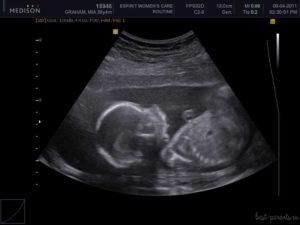

УЗИ, проведенное на 21 неделе беременности, позволяет определить пол будущего малыша, увидеть внутренние органы.

Специалист ультразвуковой диагностики оценит вероятность развития патологий, определит частоту биения сердца ребенка и состояние амниотической жидкости, установит степень двигательной активности, проведет измерения матки и плода.

При желании будущая мама сможет сама все увидеть, если УЗИ проведут в 3Д или 4Д формате, и сделать первую фотографию ребенка.

Ультразвуковое исследование на 21-й неделе беременности позволяет детально осмотреть плод, оценить его развитие, определить пол, а также проверить обвитие пуповиной, состояние плаценты, уровень околоплодных вод и матки. Кровоток в сосудах матки и плаценты анализируется с помощью допплерографии. Процедура безопасна, безболезненна и важна для специалистов.

На 21-й неделе беременности при ультразвуковом исследовании пол ребенка становится ясным. У девочек половые органы представлены двумя параллельными линиями, у мальчиков — небольшим копьевидным выступом.

На 21-й неделе беременности органы и системы плода сформированы, постепенно увеличиваются в размерах, начинают выполнять свою функцию. Головной мозг функционирует активнее – малыш улыбается, хмурится, совершает хватательные движения ручками, перебирает ножками.